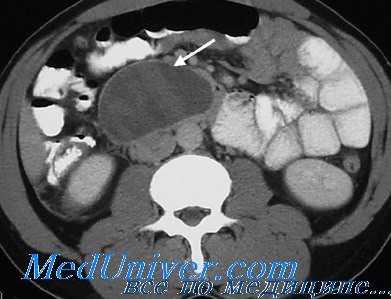

При КТ с контрастным усилением у всех больных АП было обнаружено фокальное или диффузное увеличение поджелудочной железы (ПЖ), нечеткость ее контуров, чуть реже - очаги задержки жидкости в железе (83 %), инфильтрация парапанкреатической клетчатки (70 %), очаги задержки жидкости вне ПЖ плотностью 5-15 ед. и размерами 2-3 см: единичные (18 %), два и более (30 %). В 31,0 % случаев АП изменения, обнаруженные при КТ, соответствовали стадии C по шкале Balthazar-Ranson, в 50,0 % - D, в 19,0 % - E.

При ИП стадию С по шкале Balthazar-Ranson диагностировали в 14,3 %, D - в 18,4 %, E - в 40,8 %. У всех выявлено фокальное или диффузное увеличение ПЖ, нечеткость ее контуров, инфильтрация парапанкреатической клетчатки с наличием секвестров (84,6 %), очаги задержки жидкости в ПЖ - (66,6 %). Очаги скопления жидкости вне ПЖ плотностью 15-20 ед., размерами 5 см и более встречались чаще: единичные в 22,7 %, два и более - 29,5 %.

Компьютерная томография с контрастированием дает косвенные признаки для дифференциальной диагностики асептического и инфицированного панкреонекроза - обширные скопления жидкости вне поджелудочной железы плотностью 15-20 ед. Инфицирование при панкреонекрозе, несмотря на интенсивное консервативное лечение, произошло у трети пациентов. Летальность после оперативного лечения, выполненного в ранние сроки с момента заболевания, была значимо выше, чем после хирургических вмешательств, выполненных в более поздние сроки. Исходом панкреонекроза в 25,3 % было формирование постнекротических (17,6 %) кист и панкреатических свищей (7,7 %).